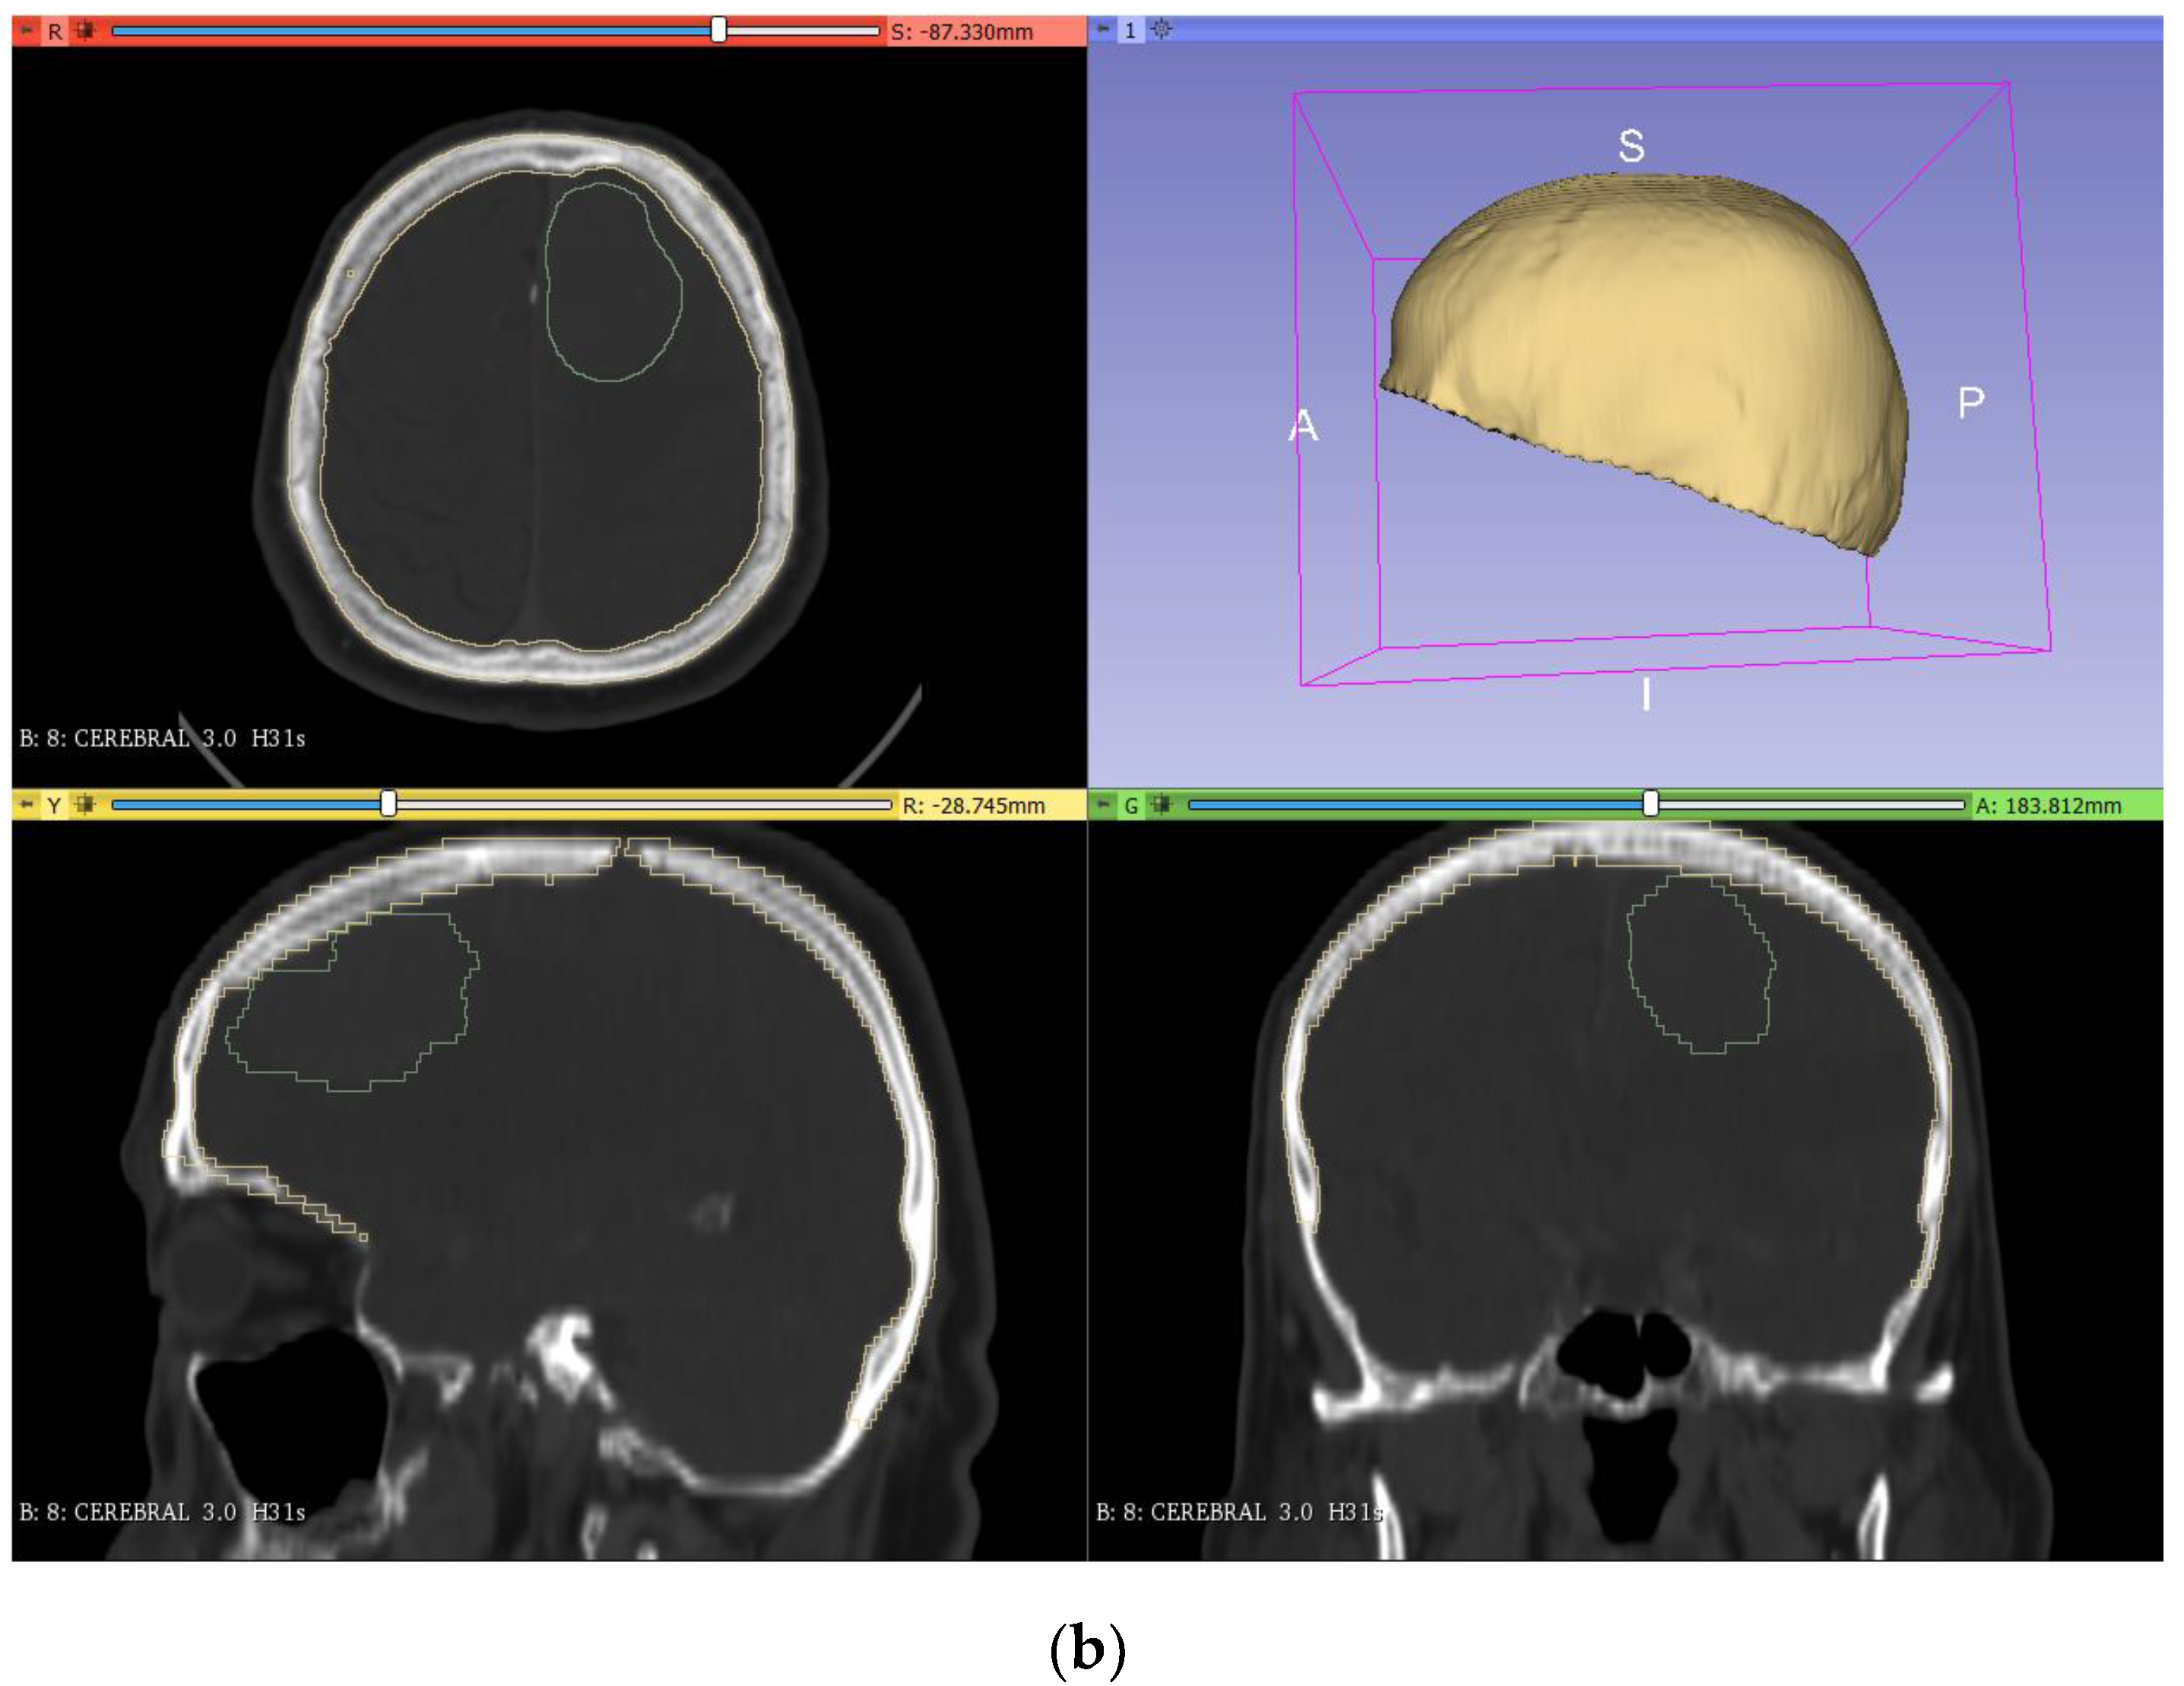

As mentioned above, the production of a tumor prototype requires a mold where the silicone mixture has to be poured to obtain the desired geometric model. To do this, the model was segmented (Figure 3a) using a similar approach to that applied for the bone segmentation. However, since the tumor is not easily differentiated from the brain, more manual work was needed. The first step was to apply the ‘threshold’ tool in the segment editor to try to select all the pixels corresponding to the tumor by adjusting the range of application. As the previous step was not accurate due to the color similarity between the brain and tumor, the ‘erase’ and ‘paint’ tools were used, layer by layer, to adjust the segmented area (‘erase’ to remove areas and ‘paint’ to add new areas to the segment). After this, a copy of the segmented model was made (‘logical operators’, ‘copy’ operation) with an added thickness of 10 mm (‘margin’ tool). Then, the original model was subtracted to the increased model (‘logical operators’ tool, ‘subtract’ operation), leaving a hollow segmented model as a mold (Figure 3b).

Figure 3.

Segmentation (a) and creation of the tumor mold (b) from the DICOM images in 3DSlicer.